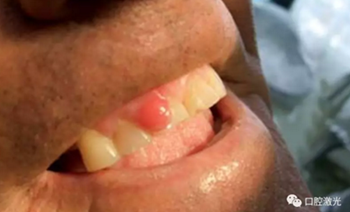

術(shù)后1周、4周、6個(gè)月以及1年對(duì)患者進(jìn)行追蹤觀察。1周復(fù)診時(shí),重點(diǎn)了解疼痛、出血以及水腫的情況。其結(jié)果為沒有出現(xiàn)上述情況。所有的患者都可以術(shù)后立即恢復(fù)正常的生活、學(xué)習(xí)、工作活動(dòng)。并且,術(shù)后沒有使用止疼藥和消炎藥。在4周時(shí),評(píng)估傷口的愈合情況,所有的患者都恢復(fù)很好,沒有出現(xiàn)并發(fā)癥現(xiàn)象。在6個(gè)月至1年期間,沒有出現(xiàn)任何形式的復(fù)發(fā)。因此,患者對(duì)激光手術(shù)的效果評(píng)價(jià)十分高。

通過口腔激光對(duì)齦瘤進(jìn)行手術(shù)切除有著眾多優(yōu)勢(shì)。其中,由于對(duì)血紅蛋白的吸收率很高,半導(dǎo)體激光有著優(yōu)秀的凝血效果。不但術(shù)中出血量大大減少,同時(shí)給醫(yī)生提供了一個(gè)良好的手術(shù)視野。術(shù)后的優(yōu)勢(shì)也是顯而易見的,傷口愈合的速度更快,沒有疼痛和水腫的發(fā)生。大大縮短的手術(shù)時(shí)間,減少了患者對(duì)手術(shù)治療的恐懼心理。因此對(duì)于患者和醫(yī)生來說都十分受益于口腔激光。